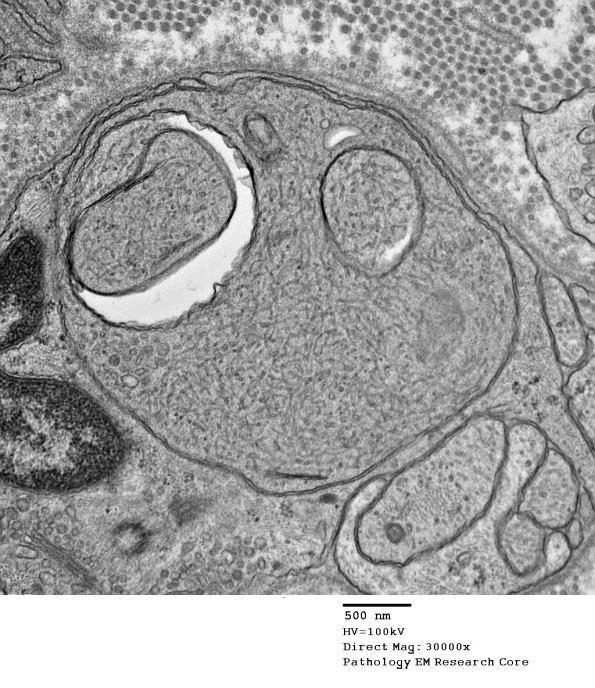

This nerve exhibited axon loss, regenerative clusters and typical neuroaxonal dystrophy involving scattered axons. The cleft is common in dystrophic axons as are the tubulovesicular elements. (electron micrographs)